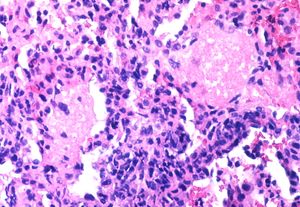

HIV 자체는 숙주의 면역 반응을 피하기 위해 끊임없이 변이하는 능력을 가지고 있다.[128][37] HIV에 감염된 CD4+ T 세포의 비율이 특정 시점에 높지 않더라도, 감염된 세포의 빠른 사멸과 새로운 세포 감염이 지속적으로 일어나 면역 체계를 점진적으로 파괴한다.[38] 대식세포 등 다른 면역 세포 역시 HIV의 저장소 역할을 한다. 또한 HIV는 면역계를 직접 억제하는 단백질을 분비하기도 한다. 예를 들어, HIV의 외피 단백질인 gp120은 건강한 T 세포의 CD4 수용체에 결합하여 정상적인 기능을 방해하며, Tat 단백질은 T 세포 활성을 억제하는 것으로 나타났다. 감염된 림프구는 Fas 리간드를 발현하여 주변의 비감염 T 세포까지 사멸시키는 "구경꾼 살해" 효과를 유발하기도 하는데, 이는 소수의 감염된 세포만으로도 면역계 전체에 큰 손상을 줄 수 있음을 보여준다.[39]

그러나 HIV 감염 후 증상이 나타나지 않거나 늦게 나타난다고 해서 HIV가 에이즈의 원인이 아니라는 의미는 아니다. HIV는 인체의 면역계를 공격하는 바이러스로, 특히 면역 기능에 중요한 역할을 하는 CD4+ T세포를 주된 표적으로 삼는다. 비록 특정 시점에 감염된 CD4+ T 세포의 비율 자체는 높지 않을 수 있지만, 연구에 따르면 질병이 진행되는 동안 감염된 세포가 죽고 새로운 세포가 감염되는 과정이 매우 빠르게 반복된다.[129][38] 대식세포와 같은 다른 종류의 세포들도 HIV에 감염될 수 있으며, 이들은 바이러스가 숨어있는 저장소 역할을 할 수 있다.

또한 다른 바이러스와 마찬가지로 HIV는 면역계를 방해하는 단백질을 분비하여 면역계를 억제할 수 있다. 예를 들어, HIV의 외피 단백질인 gp120은 바이러스 입자에서 떨어져 나가 건강한 T 세포의 CD4 수용체에 결합한다. 이것은 이러한 신호 수용체의 정상적인 기능을 방해한다. 또 다른 HIV 단백질인 Tat는 T 세포 활성을 억제하는 것으로 나타났다.

감염된 림프구는 Fas 리간드를 발현하는데, 이것은 Fas 수용체를 발현하는 주변의 비감염 T 세포의 사멸을 유발하는 세포 표면 단백질이다.[130][39] 이러한 "구경꾼 살해(Bystander killing)" 효과는 소수의 감염된 세포만으로도 면역계에 큰 피해를 줄 수 있음을 보여준다.

HIV가 면역체계를 파괴하는 방식은 복합적이다.

- HIV는 주로 면역계의 핵심 세포인 CD4+ T세포를 감염시킨다. 특정 시점에 감염된 세포의 비율 자체는 높지 않을 수 있지만, 질병이 진행되는 동안 감염된 세포가 죽고 새로운 세포가 감염되는 과정이 매우 빠르게 반복된다.[129][38] 대식세포와 같은 다른 종류의 세포들도 HIV에 감염되며 바이러스의 저장소 역할을 할 수 있다.

- HIV는 면역계를 방해하는 단백질을 분비한다. 예를 들어, HIV의 외피 단백질인 gp120은 바이러스 입자에서 떨어져 나와 건강한 T세포의 CD4 수용체에 결합하여 세포의 정상적인 신호 전달 기능을 방해한다. 또 다른 HIV 단백질인 Tat는 T세포의 활성을 억제하는 것으로 밝혀졌다.

- 감염된 림프구는 세포 표면에 Fas 리간드를 발현시킨다. 이 단백질은 주변에 있는, 감염되지 않은 T세포 중 Fas 수용체를 가진 세포들의 자살(apoptosis)을 유도한다.[130][39] "구경꾼 살해(bystander killing)"라고 불리는 이 현상은 소수의 세포만 HIV에 감염되어도 주변의 건강한 면역 세포까지 파괴하여 면역계 전체에 심각한 손상을 줄 수 있음을 보여준다.